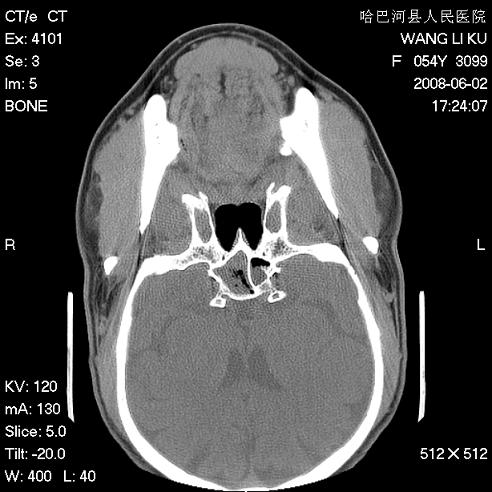

标题: CT13803:反复性鼻塞、流涕一年余 [打印本页]

标题: CT13803:反复性鼻塞、流涕一年余

副鼻窦炎,右上额窦积脓。左眼肌锥内见致密影,视神經受压

1.全组副鼻窦炎2.双侧上颌窦积液

1)全副鼻窦炎(左侧上颌窦黏膜下囊肿或息肉)。2)左眼眶肌锥内不规则小结节状软组织密度影;考虑为小血管瘤可能。建议行ct增强扫描检查。

全组副鼻窦炎,左侧肌锥内不规则形软组织肿块影,与眼外肌密度相当,左侧视神经受压,肿块与视神经及眼外肌分界清晰,眼外肌无增粗,眶壁无破坏,球后脂肪间隙不模糊,考虑良性改变,小血管瘤或神经源性肿瘤可能,建议增强扫描。

谢谢,增强扫描做了,眶内病灶与海绵窦同步明显强化,血管瘤